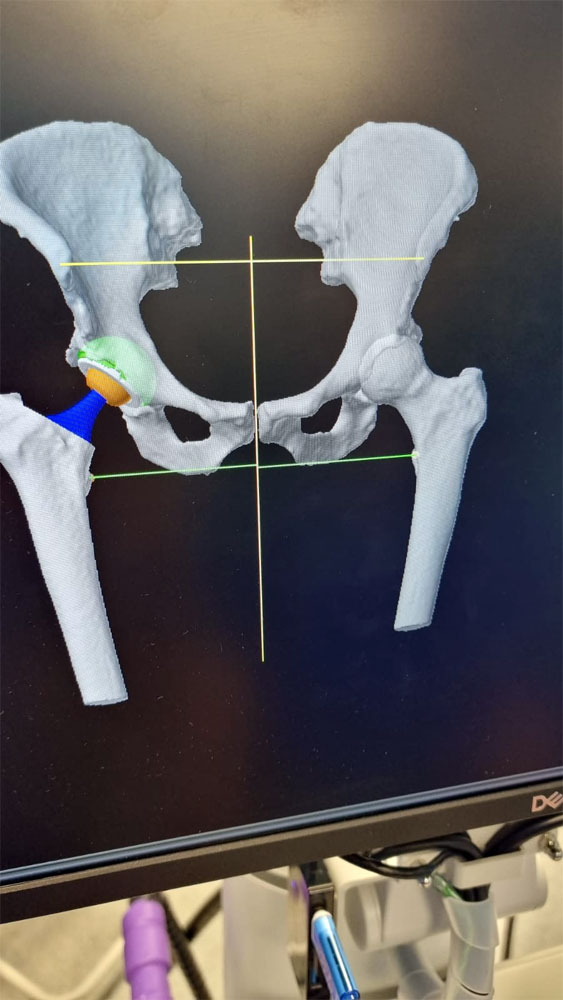

Внедрение методов интраоперационной компьютерной навигации в ортопедии и нейрохирургии

Успешно интегрируется в лечебный процесс технология интраоперационной компьютерной навигации. Стартовав в травматологии и ортопедии, для максимально точного расчета объема вмешательства и прецизионности его выполнения при эндопротезировании суставов, затем в нейрохирургии при выполнении операций на головном и спинном мозге, в настоящее время технология не менее успешно используется в челюстно-лицевой хирургии при коррекции сложных дефектов орбиты, сочетанных травмах и пр. В нашей стране так широко и разнообразно метод применяется только в Пироговском Центре.